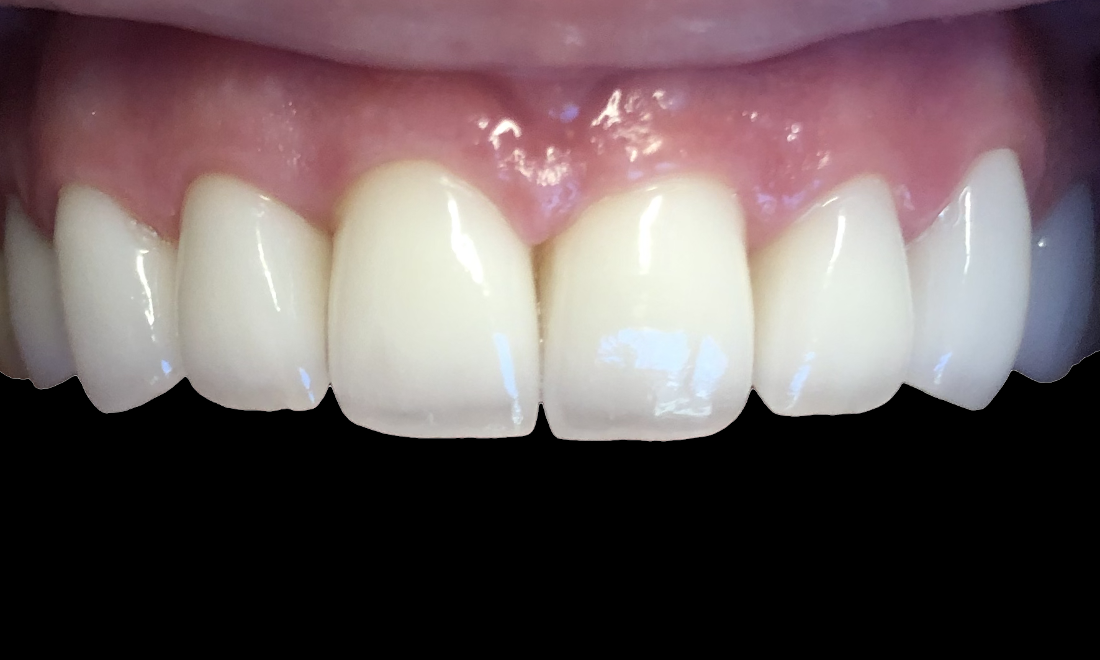

Smile Makeover

This patient suffered from cavities on her front teeth that affected her smile for years.  We placed ceramic crowns to restore her beautiful smile.